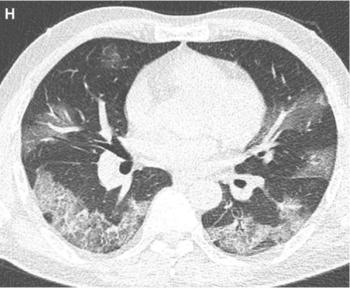

In a recently published study involving hospitalized patients with COVID-19, researchers compared chest CT findings of vaccinated, partially vaccinated, and unvaccinated patients.